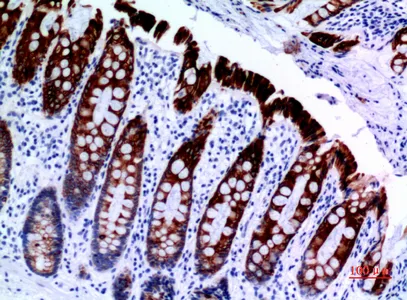

Cytokeratin 8 Rabbit Polyclonal Antibody

Cat: APRab09760

Size1:50μl Price1:$118

Size2:100μl Price2:$220

Size3:500μl Price3:$980

Size2:100μl Price2:$220

Size3:500μl Price3:$980